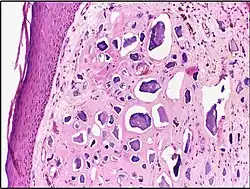

![]() |

Mucinous cystadenoma | Micrograph showing Mucinous Cystadenoma of ovary. The cyst wall is lined by tall columnar epithelium and filled with mucin. | Category: Histopathology of mucinous cystadenoma | Mucinous cystadenoma |